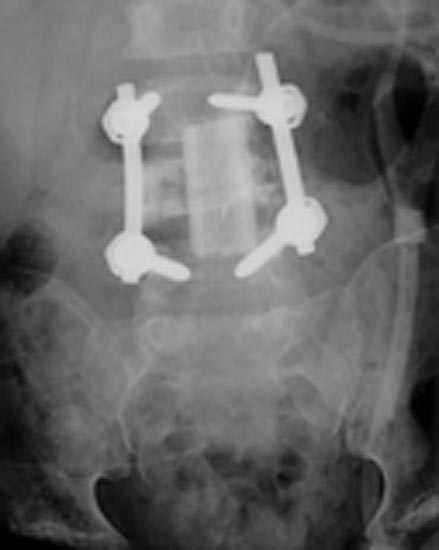

Rayos X frontales de la columna lumbar mostrando tornillos pediculares en L-3 y L-5 con varillas conectores a cada lad. Un aloinjerto anterior de trabéculas óseas es utilizado para tratar un neuroblastoma (tumor maligno compuesto de neuroblastos) metastásico (invasivo) en el cuerpo vertebral de L-4.

Nota: Las imágenes se muestra para fines ilustrativos. No trate de sacar conclusiones comparando esta imagen con otras en el sitio. Solamente los radiólogos calificados deben interpretar las imágenes.